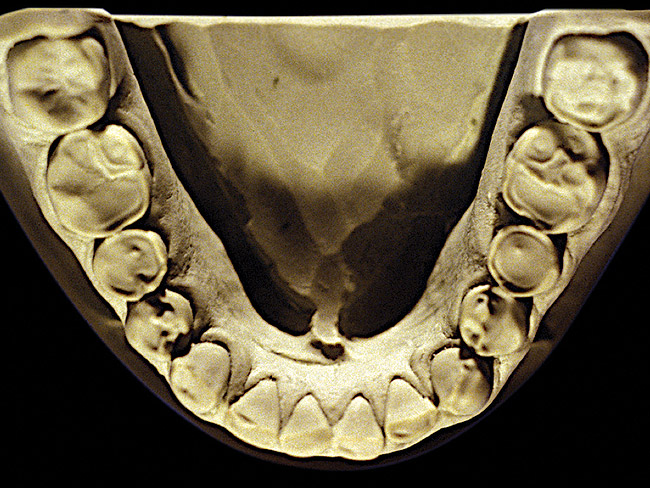

The patient shown in Figure 3 and Figure 4 exhibited severe NCLTS from bruxism. Examination of the casts indicated that the NCLTS was progressively greater toward the anterior teeth. Cupping and cratering was not present because there was no secondary cause. Figure 5 and Figure 6 detail another bruxism patient, but to a lesser degree and one with cupping/cratering caused by toothpaste. The cups or craters were not caused from bruxism because the teeth could not touch the bottom of the invaginations. In both featured patients, upon hand-articulating the casts, the NCLTS facets matched up and the diagnosis of bruxism was confirmed.

Figure 4  Advanced NCLTS from bruxism, maxillary arch.

Figure 4

Figure 5  Moderate NCLTS from bruxism, maxillary arch.

Figure 5

Figure 6  Moderate NCLTS from bruxism, mandibular arch.

Figure 6